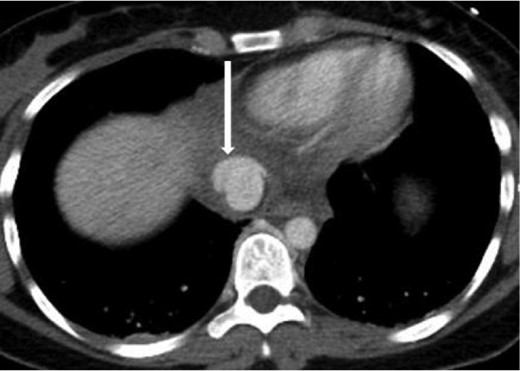

A 20-year-old female was the restrained driver of a vehicle traveling ∼45 miles per hour when her vehicle crashed into a city bus. She was extricated on scene by emergency responders and brought to the trauma bay alert, oriented and in stable condition complaining of pain on deep inspiration as well as left leg pain. She denied any abdominal pain or light-headedness. Vital signs on arrival were heart rate of 115 bpm, respiratory rate of 20 breaths per minute and blood pressure of 101/76 mmHg; her Glasgow coma scale was 15. The initial chest radiograph showed a small, right-sided pneumothorax and pulmonary contusions. Two radiographic views of the left leg revealed comminuted, mildly displaced tibia and fibula fractures. Computed tomography (CT) scans of the brain and neck were unremarkable. A contrast-enhanced chest CT scan demonstrated non-displaced right lateral second and third rib fractures, right upper lobe pulmonary contusions with laceration and a small pneumothorax, partially visualized grade 5 liver laceration with active contrast extravasation, and an acute, traumatic supradiaphragmatic IVC injury with an associated moderate hematoma and contrast extravasation that appeared to be contained, as seen in Figs 1 and 2. In view of incompletely imaged critical findings of the upper abdomen and continued hemodynamic stability of the patient, a dedicated abdomen and pelvis CT scan, seen in Figs 3–5, was performed 20 min later, which showed a stable 1.3 cm pseudoaneurysm of the supradiaphragmatic IVC without extension into the pericardium, stable moderate pericaval hematoma surrounding the injury, stable grade 5 liver laceration and a trace amount of fluid in the peritoneal cavity. A liver transplant surgeon and a cardiovascular surgeon were consulted due to the presence of acute traumatic suprahepatic IVC pseudoaneurysm.

Sagittal contrast-enhanced CT of the abdomen performed 30 min after the initial CT of the chest showing persistence of the abnormal contour of the supradiaphragmatic IVC with contrast extravasation confined laterally and ventrally (arrow), nonexpanding pericaval hematoma.